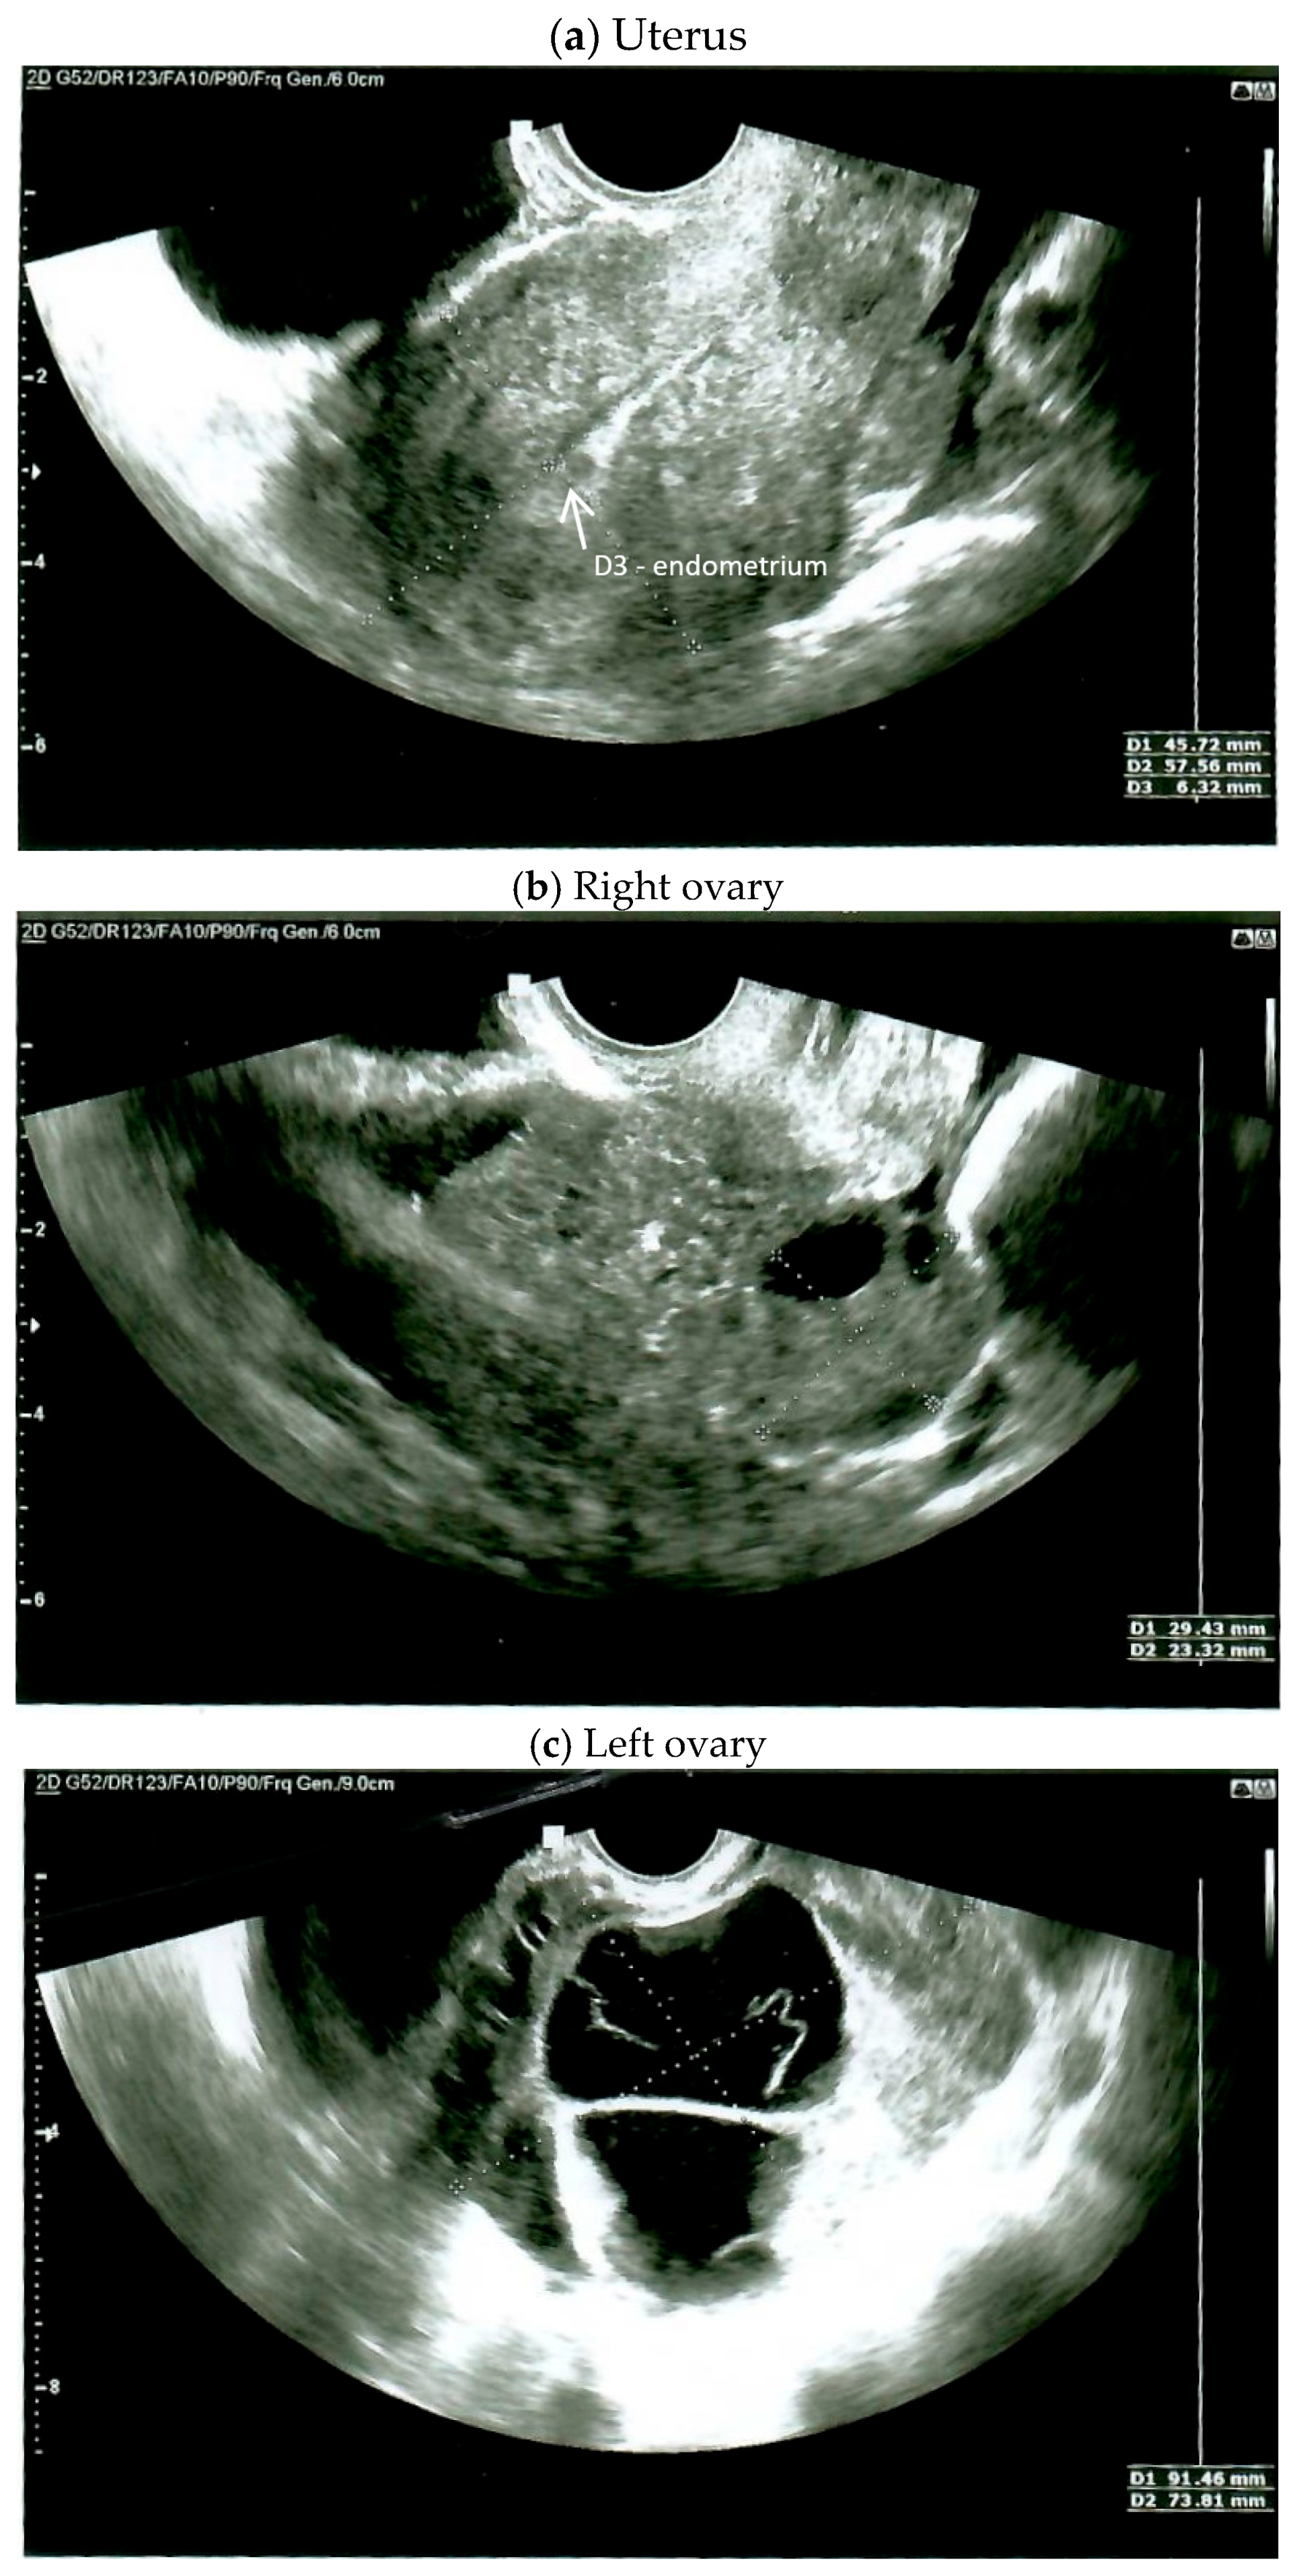

2. Case Report